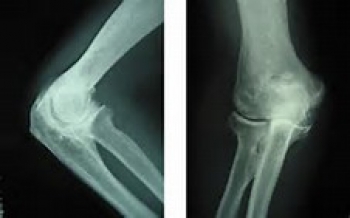

問診(職業の他、運動の経験などの問診)、診察、X線検査などを行います。

X線撮影で骨の変形具合を確認します。

関節リウマチや神経の病気との鑑別が必要になります。